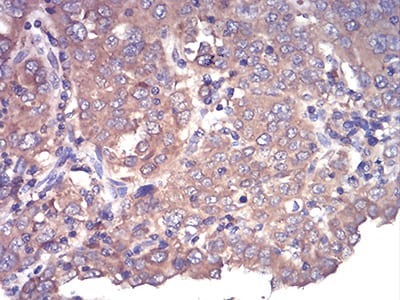

Immunohistochemical analysis of paraffin-embedded human cervical cancer tissues using CFHR5 mouse mAb with DAB staining.

Immunohistochemical analysis of paraffin-embedded human endometrial cancer tissues using CFHR5 mouse mAb with DAB staining.